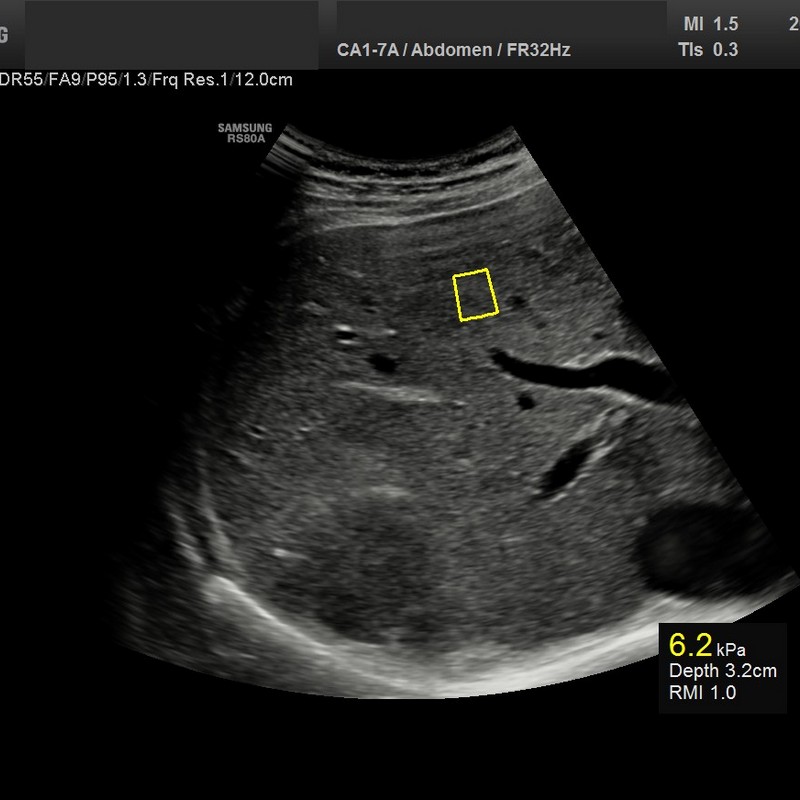

• USG jamy brzusznej

z oceną wątroby, trzustki, nerek, śledziony, pęcherza, gruczołu krokowego, dużych naczyń jamy brzusznej oraz przestrzeni okołoaortalnej.

• USG jamy brzusznej z oceną wątroby, trzustki, nerek, śledziony, pęcherza, gruczołu krokowego, dużych naczyń jamy brzusznej oraz przestrzeni okołoaortalnej

• zmian miąższowych wątroby

• oceny włóknienia wątroby (choroby wirusowe, marskość)

• ocena stłuszczenia wątroby

• diagnostyka NADCIŚNIENIA WROTNEGO - badanie śledziony

Badanie elastograficzne można wykonać w naszej pracowni jako rozszerzenie badania USG tarczycy i piersi (ocena guzków), a także jako samodzielne badanie – elastografia wątroby w celu oceny włóknienia(stosowana u nas metoda elastrografii 2D-SWE jest znacznie dokładniejsza od dotychczas stosowanej metody TE [FIBROSCAN®].